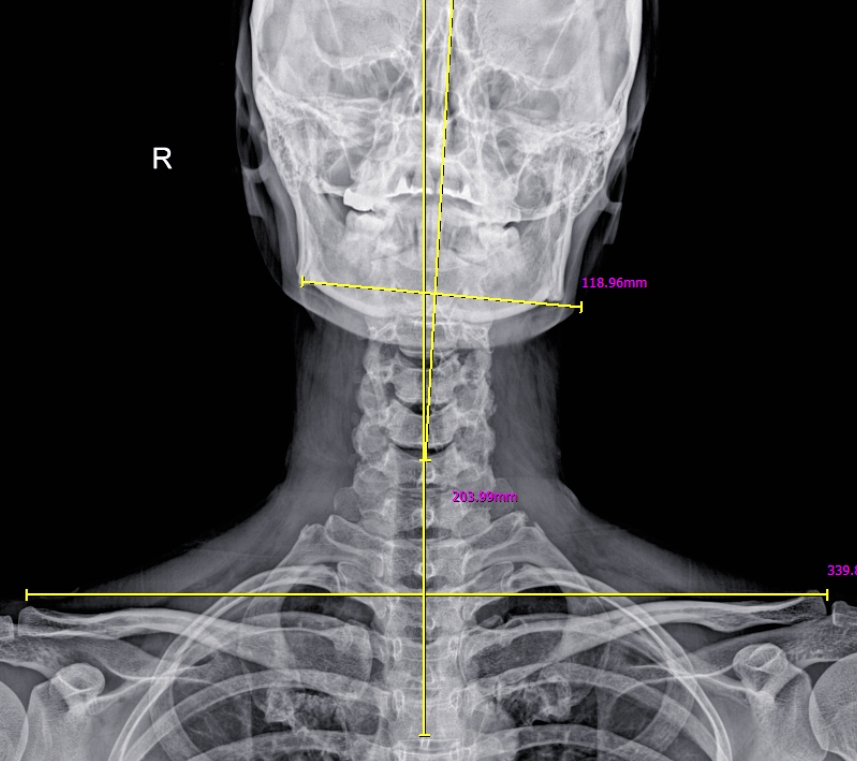

여러분의 발은 가만히 있는 상태와 움직이는 상태에서 매우 다른 모습을 보입니다. 맞춤 깔창을 선택할 때 단순히 발의 정적인 모양만 측정하는 것은 큰 위험을 초래할 수 있습니다. 걸을 때는 복잡한 생체역학적인 움직임이 이루어지기 때문입니다. 단순히 서 있는 상태의 발 모양만으로 깔창을 제작하면, 실제 보행 중에 발이 안쪽 혹은 바깥쪽으로 과도하게 회전할 가능성이 큽니다. 이를 과회내(Overpronation)이나 과회외(Supination)라고 하며, 이로 인해 발목, 무릎, 고관절 등 다양한 부위의 통증이 만성화될 수 있습니다. 저희 시지다나아마취통증의학과의원에서는 이와 같은 문제를 방지하기 위해 철저한 보행 분석(Gait Analysis)를 통해 발의 동적 움직임을 면밀히 평가합니다. 이를 통해 환자 여러분에게 맞춤화된 깔창을 제공하여 최상의 컨디션을 유지할 수 있도록 도와드리고 있습니다.